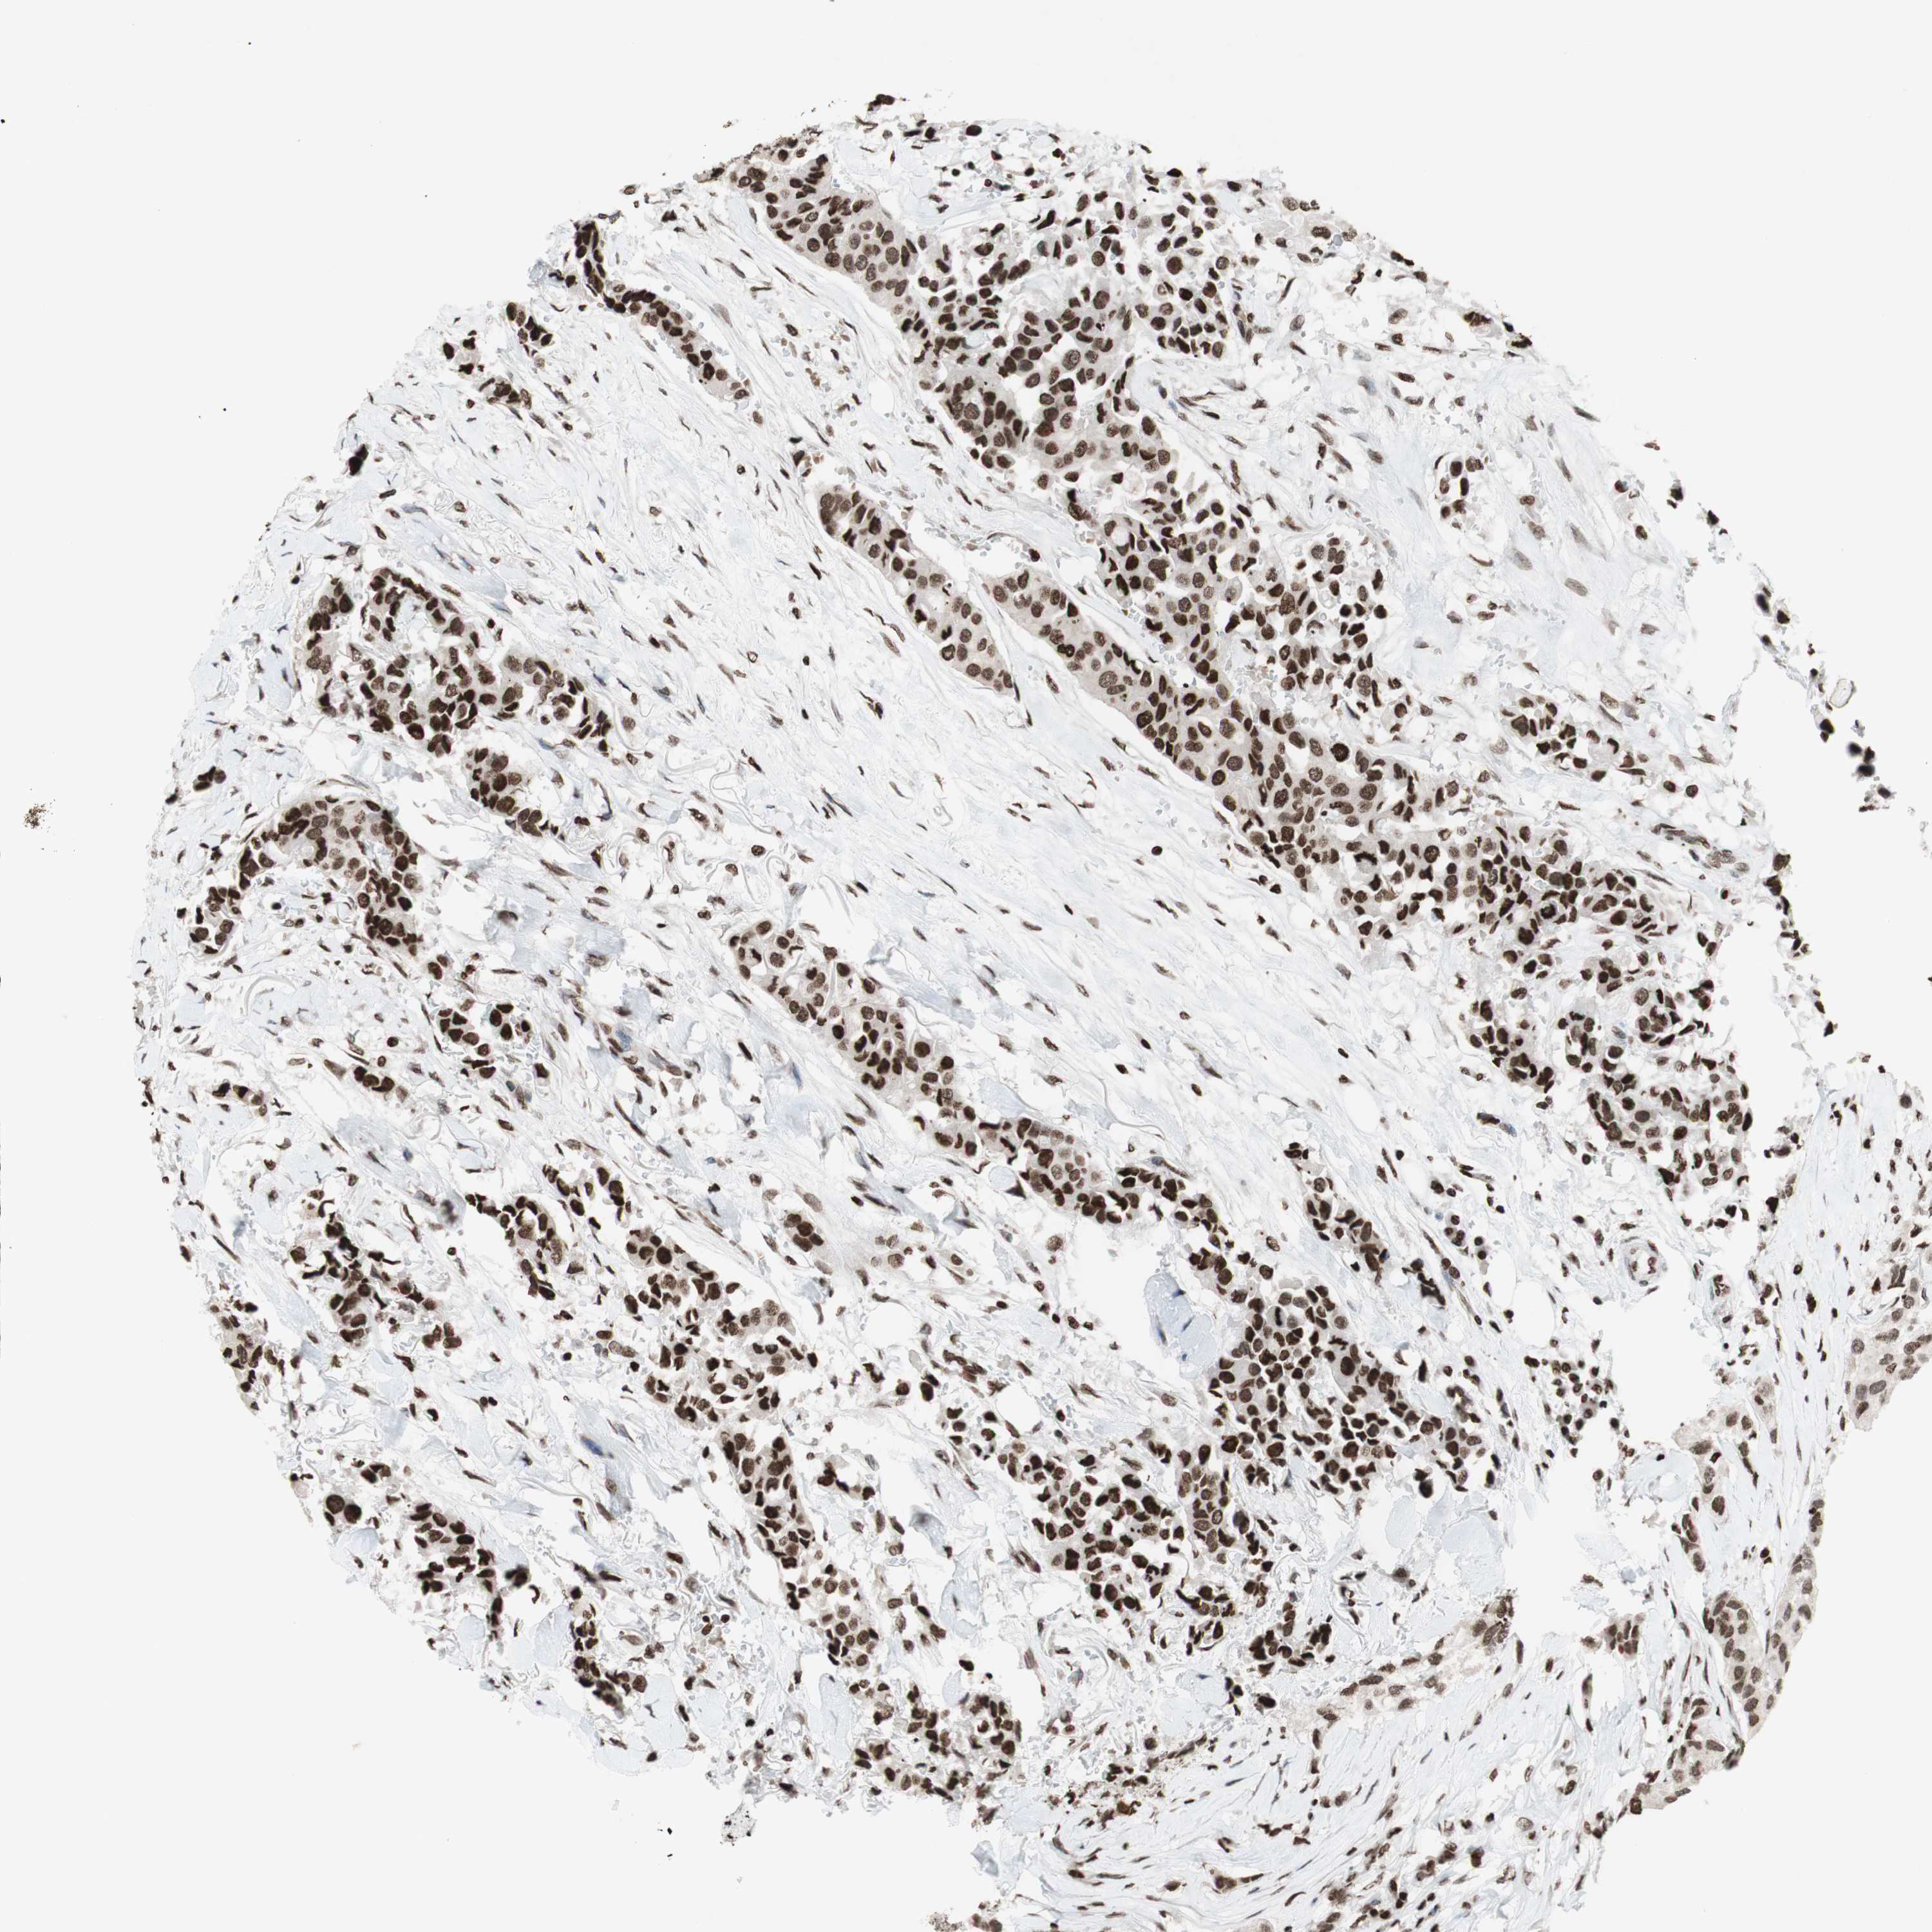

BRCA TCGA BRCA VALIDATION PROTEIN EXPRESSION

ANTIBODIES

AND

VALIDATION